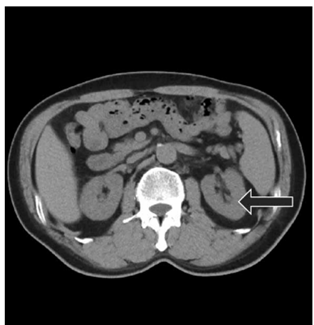

Observe a imagem a seguir: Qual alternativa representa

o corte visualizado na imagem de tomografia a seguir e o

órgão apontado pela seta?

Qual alternativa representa o corte visualizado na imagem de tomografia apresentada e o órgão apontado pela seta?